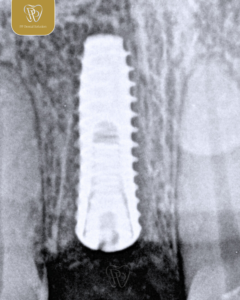

Implant

Gigi yang hilang bukan hanya memengaruhi penampilan, tapi juga fungsi mengunyah dan kesehatan gigi lainnya.

Implan gigi hadir sebagai solusi permanen yang menyerupai gigi asli, baik dari segi fungsi maupun estetika.

Masih ingin menunda perawatan? Sobat PP Dental, lebih baik mengganti gigi yang hilang sejak dini agar kenyamanan dan kepercayaan diri tetap terjaga 🦷✨